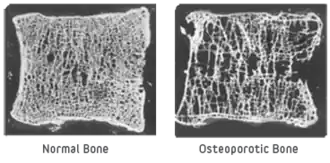

Hyperparathyroidism

Because the formation of PTH regulates the calcium level in the blood, it can affect all areas of the body. The overactivity of a parathyroid gland is known as hyperparathyroidism. It is unknown what directly causes hyperparathyroidism. However there are many factors that can cause over-secretion of PTH. The further consequence of this disorder can be osteopenia, or even osteoporosis, which is the loss of bone density.[13] This leaves bones more porous, fragile, and likely to experience fracture. This can be detected by usage of dual-energy X-ray absorptiometry (DEXA). Interesting enough, a derivative of synthetic PTH is often given to patients with osteoporosis to combat the disease.[14]